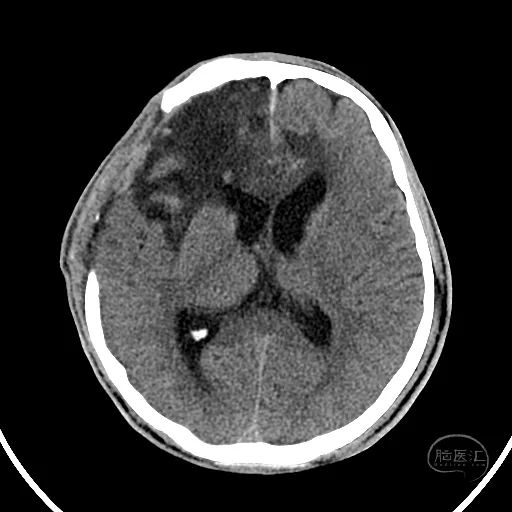

术后18天复查颅脑CT,显示小脑半球恢复良好,第四脑室清晰。

硬膜外血肿基本吸收。

额叶水肿减轻。

脑室稍扩张,骨窗张力较低。

患者GCS评分8分,已转入普通病房,继续康复治疗。